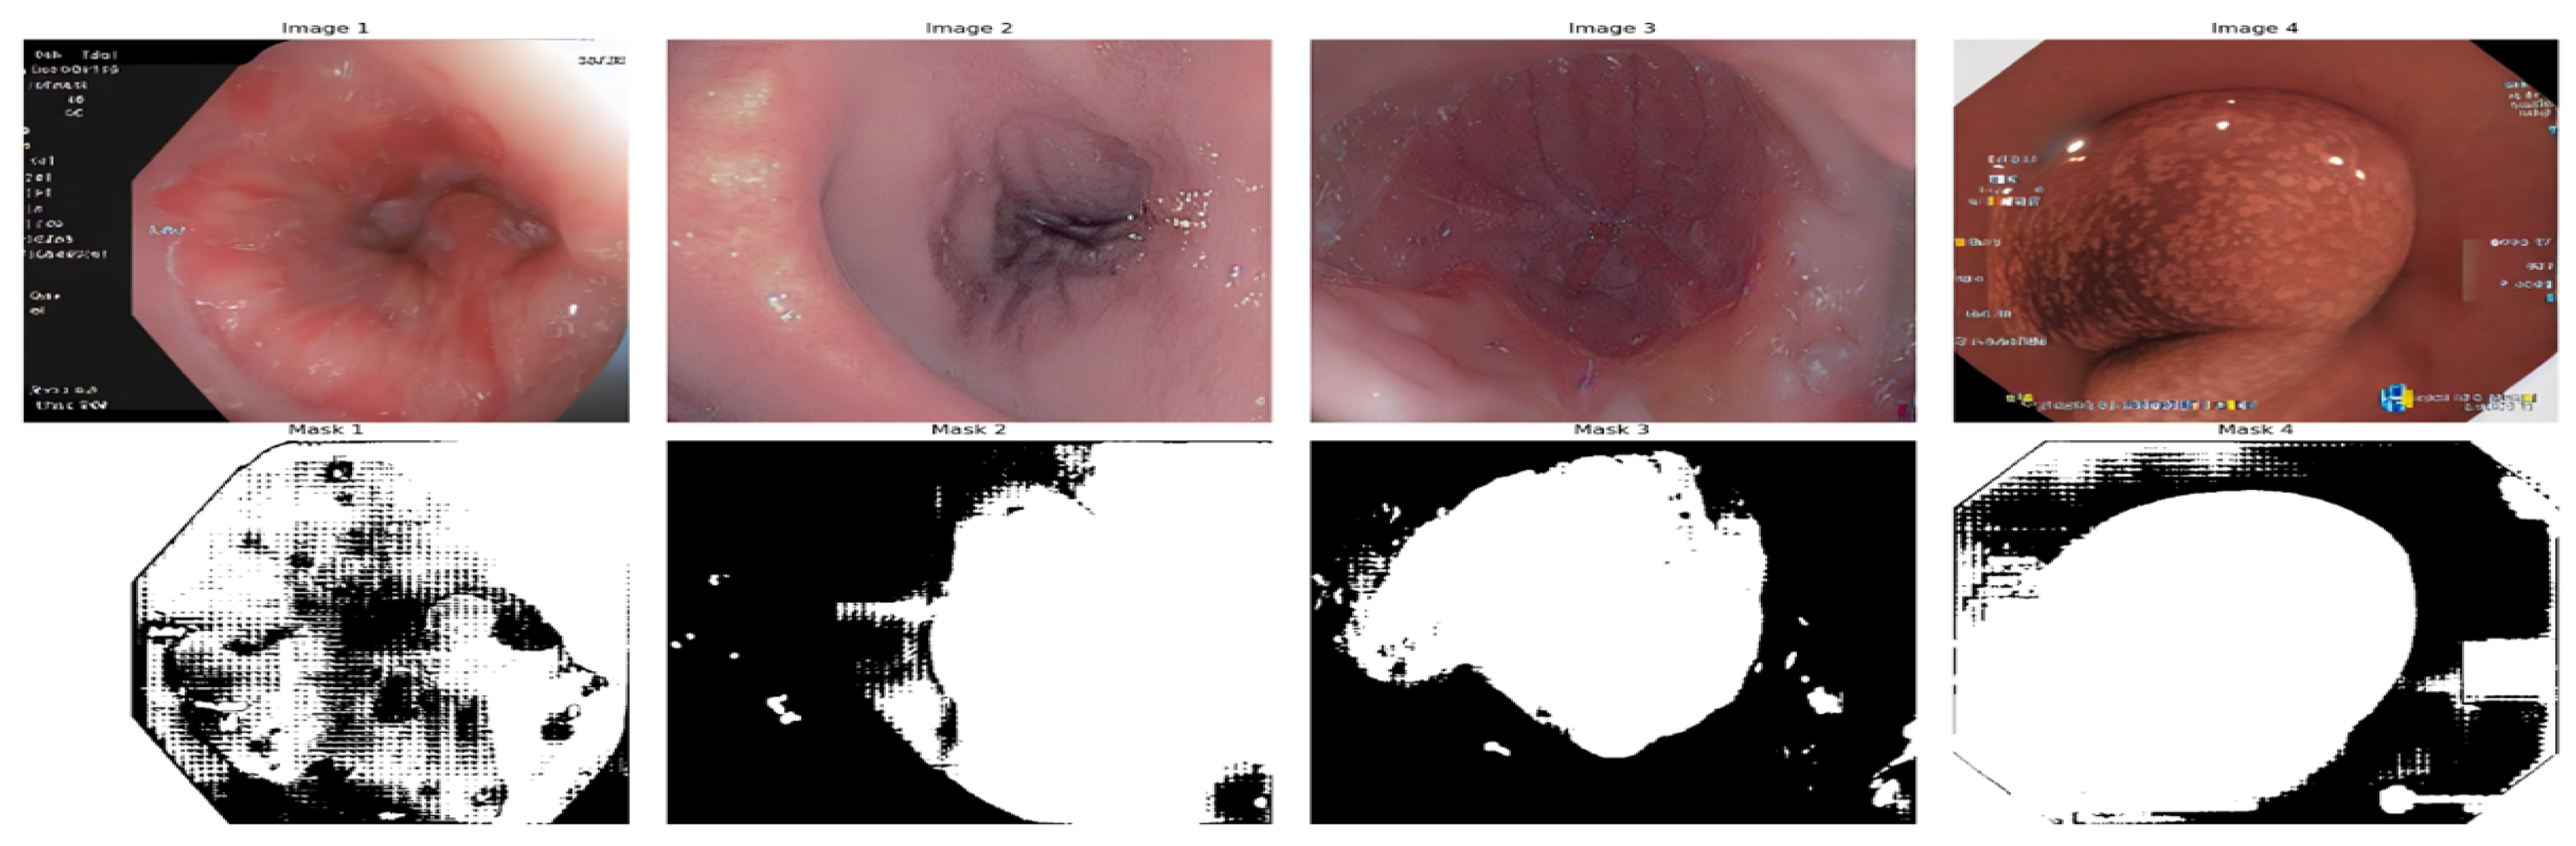

Image masks were created for shapes identified with the Segment Anything Model (SAM) [54]. The technique starts with initializing SAM with a pre-trained checkpoint and finds circles and outlines in the input image that mimic polyps. Input points are produced along the boundary of every form found. see Figure 9

Once these points are accumulated, the SAM predictor creates a mask. To anticipate segmentation masks, SAM uses input points and their corresponding labels, such as background and foreground. This enables SAM to produce precise masks for each shape by using reduced contours and points from known circles as input. The final mask for the entire image was created by combining these many masks, as shown in Figure 16.

Figure 9. Synthetic Image vs. Synthetic Image Mask generated by SAM